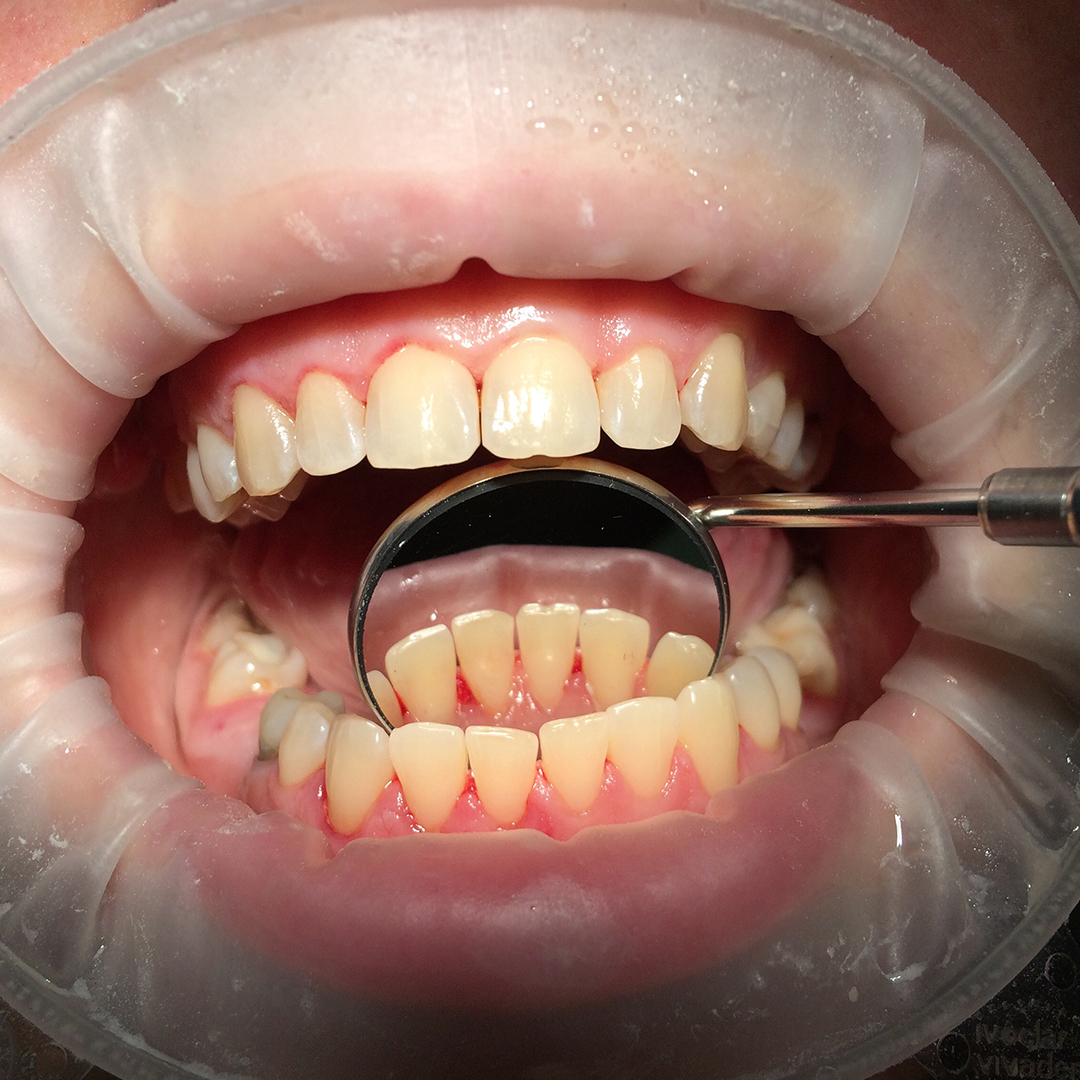

До и после лечения

В «Стоматологию Комфорта» обратилась пациентка с жалобой на твёрдые зубные отложения, которые не поддаются удалению в домашних условиях. В ходе личного осмотра врач стоматолог-терапевт Вахлюева Елена Сергеевна обнаружила зубной камень, затвердевший налёт и назначила пациенту профессиональную гигиену полости рта.

Процесс чистки включал в себя:

- безболезненное снятие твёрдых отложений с помощью ультразвука;

- удаление пигментации от чая, кофе, курения и других красящих продуктов;

- полировку с целью предотвращения новых отложений;

- фторирование зубов с использованием специальных паст для укрепления эмали.